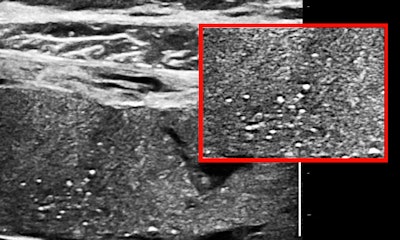

Placental architecture

Some or most of the placenta is accessible transabdominally for 15- to 20-MHz scanning in the third trimester with modern ultrasound units, especially when the placenta is anterior or anterolateral, or fundal. Viewed in this way, a normal placenta is far from homogeneous. Neglecting fluid spaces, vascular voids, infarcts, or other anechoic or hypoechoic patches, the improvement in contrast enables seeing punctate reflectors, representing corked-off vessels, and later in the course of this pathology, patches of increased reflectivity that imply, as elsewhere, sclerosis (see figures 1 and 2). Small-vessel disease of the placenta is of the greatest clinical importance.

So if you start seeing punctate reflectors in the placenta, you will think that a thrombophilia panel is a good idea, or, alternatively, if there is an abnormal maternal thrombophilia profile early in pregnancy, some sort of ultrasound surveillance for the emergence of small-vessel disease should be appropriate in the third trimester. The idea is to identify the risk and act to prevent placental sclerosis and its sequellae, growth retardation and/or hypoxic compromise of individual organs.